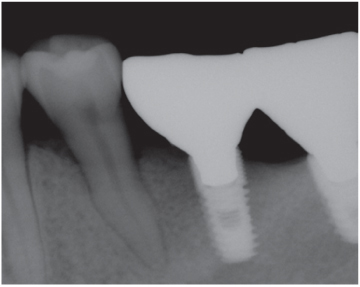

Figure 11

One year before implant surgery: Note that the posterior area of mandibular left segment was edentulous.

Figure 11 One year before implant surgery: Note that the posterior area of mandibular left segment was edentulous.